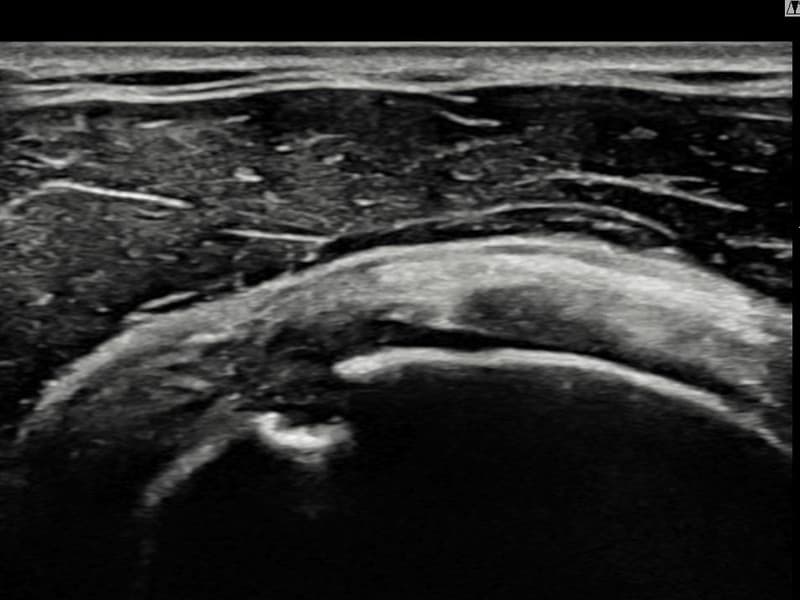

시술 전 초음파 측정 결과 파열 크기는 13mm × 6mm (힘줄 두께의 약 62% 결손)로 확인되었습니다. 시술 전 초음파에서 우측 극상근건 점액낭면측의 광범위한 에코 단절과 힘줄 두께의 현저한 감소가 확인되었습니다. 시술 후 초음파에서 점액낭면측 힘줄 경계가 선명해지고 연속성이 완전히 회복된 것이 관찰되었습니다.

40대 후반 남성 환자분으로, 골프를 즐겨 하시다 스윙 동작 중 어깨에 통증이 생겨 운동을 중단하셨습니다. 이후 통증이 악화되어 팔을 앞으로 뻗거나 위로 올리기도 어려운 상태가 되어 내원하셨습니다. 초음파 검사에서 우측 극상근건 점액낭면측의 광범위한 부분파열이 확인되었으며, 파열 두께와 범위를 고려하여 초음파 유도 하 축소봉합술을 시행하였습니다. 시술은 당일 귀가로 이루어졌으며, 이후 보조기 착용 6주 후 단계적으로 어깨 근력 강화 운동을 진행하였습니다. 시술 9주 후 추적 초음파에서 점액낭면측 힘줄 연속성이 완전히 회복된 것이 확인되어 골프 복귀에 성공하셨습니다.